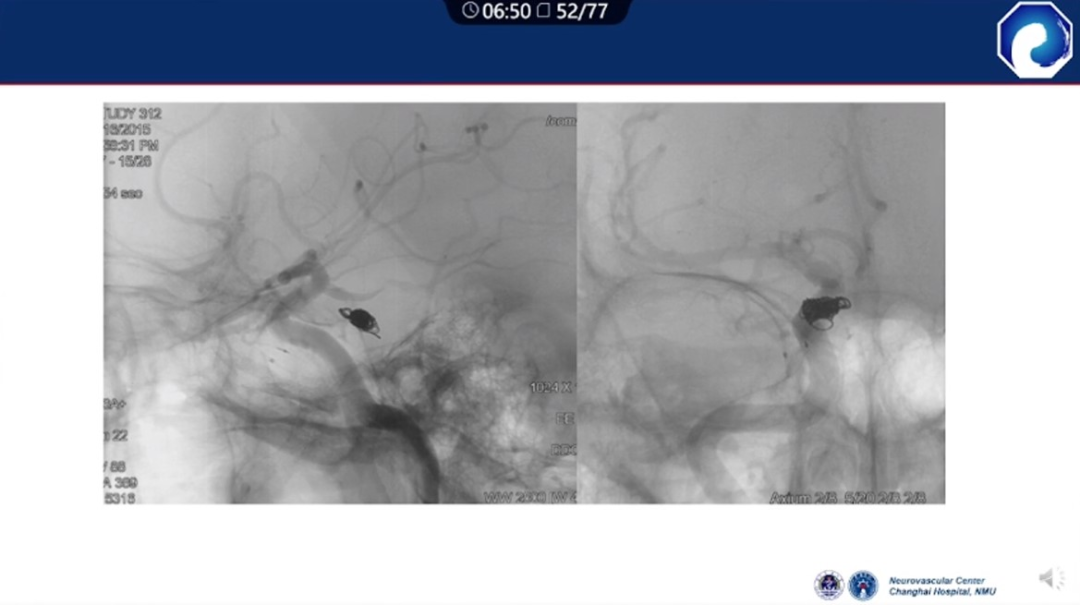

减少栓塞材料应用。

减少与颈内动脉重叠,避免栓塞材料意外栓塞。